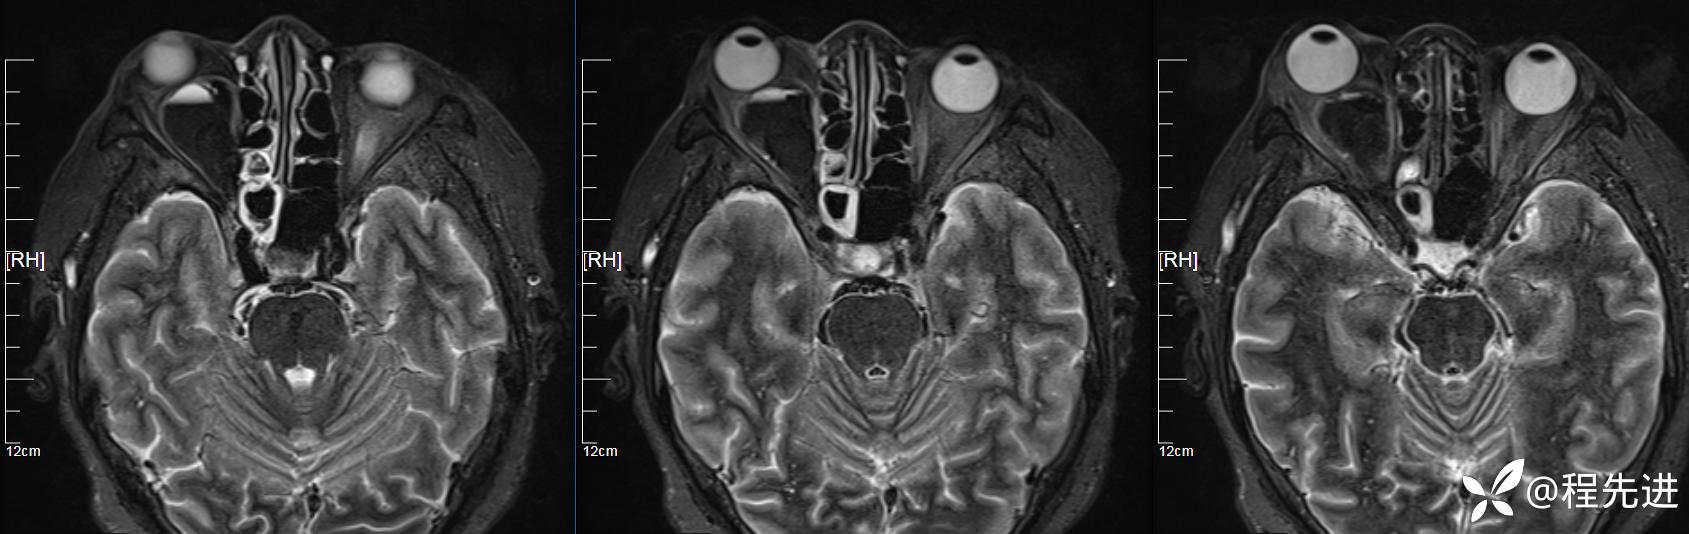

患者性别:女

患者年龄:64岁

简要病史:右眼突出10天

MR平扫+增强:

T2压脂横断位: